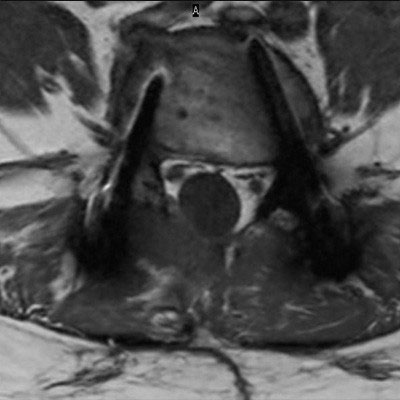

Lumbar Spine with metal implant, routine and fast

Utrecht Medical Center, The Netherlands

**Only for use with MR Safe or MR Conditional Implants by strictly following the Instructions for Use.